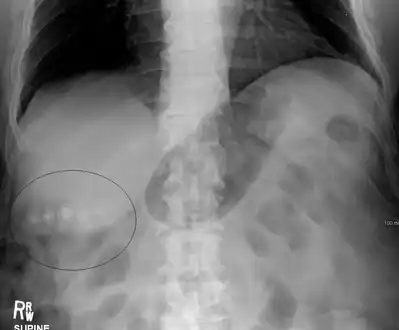

Mixed (brown pigment stones) typically contain 20–80% cholesterol (or 30–70%, according to the Japanese classification system).[36] Other common constituents are calcium carbonate, palmitate phosphate, bilirubin and other bile pigments (calcium bilirubinate, calcium palmitate and calcium stearate). Because of their calcium content, they are often radiographically visible. They typically arise secondary to infection of the biliary tract which results in the release of β-glucuronidase (by injured hepatocytes and bacteria) which hydrolyzes bilirubin glucuronides and increases the amount of unconjugated bilirubin in bile. Between 4% and 20% of stones are mixed.[3]

Diagnosis

Diagnosis is typically confirmed by abdominal ultrasound. Other imaging techniques used are ERCP and MRCP. Gallstone complications may be detected on blood tests.[2]